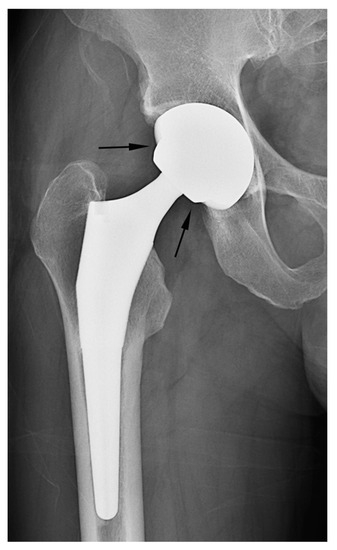

In this present study, discriminating between the two types of hip arthroplasty based on joint space narrowing or widening around the cup and/or preservation of the acetabular subchondral plate yielded the lowest diagnostic performance and inter-reader reliability among the three tested criteria. A preserved subchondral bone plate of the acetabulum and an adjacent joint space can be utilized to distinguish hemiarthroplasty from THA [2,8,19]. Under normal circumstances, this serves as a reliable indicator for distinguishing hemiarthroplasty from THA, as the fundamental difference lies in whether the acetabular articular surface is replaced. Nevertheless, when the acetabular cartilage is worn down to the extent that the outer cup of the hemiarthroplasty contacts or protrudes into the subchondral bone, resulting in acetabular erosion and migration, the absence of the adjacent cartilage joint space could lead readers to mistakenly interpret such cases as an acetabular cup placed in a reamed acetabulum in THA [7,8,19] (Figure 6a). Furthermore, in THA cases, instances of aseptic loosening or osteolysis at the bone–prosthesis interface may be misinterpreted as the adjacent cartilage joint space observed in hemiarthroplasty [2] (Figure 6b).

Figure 6.

Misinterpreted cases of acetabular sparing. (a) A simple radiograph after hemiarthroplasty showing the absence of the subchondral bone endplate and cartilage space (acetabular erosion of the bipolar cup) (arrows). When the presence of the adjacent cartilage joint space was used as the discriminator, the case was misinterpreted as THA by all readers. (b) Simple radiography after THA showing the preserved joint space and a subchondral bone plate of the acetabulum (arrow). When the presence of the adjacent cartilage joint space was used as the discriminator, two readers misinterpreted the case as a hemiarthroplasty.